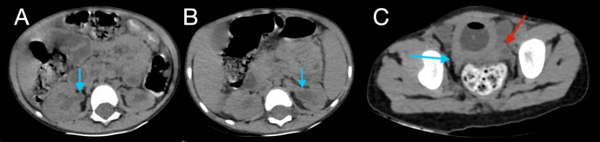

En la tomografía se evidenció presencia de S1-S2 con ausencia del resto de cuerpos sacro-coxígeos, así como hipodensidad a nivel de la médula que podría sugerir siringomielia (Figura 1). También se encontró falta de unión de algunos elementos posteriores a nivel de L5-S1 (Figura 2), lo que sugiere el diagnóstico de síndrome de regresión caudal asociado a probable siringomielia y probable vejiga neurogénica dado engrosamiento marcado de las paredes vesicales (Figura 3). Además, se encontró dilatación ureteropielocalicial de forma bilateral (Figura 4). A raíz de estos hallazgos, se solicitó una valoración por genética clínica, la cual determinó que la paciente cumple con los criterios clínicos de regresión caudal y tiene antecedentes de diabetes gestacional insulino-dependiente, lo cual es un factor de riesgo.

Figura 2. Tomografía de abdomen en ventana ósea, cortes axiales (A, B) y reconstrucción en 3D (C), donde se evidencia ausencia de unión de los elementos posteriores de L5 (flecha azul en A, flecha verde en C) y S1 (flecha azul en B y C) y ausencia de elementos sacro-coccígeos (flecha roja en C).

En este caso, se encontró una ausencia parcial sacro coxígea con preservación de S1 (Figura 1), asociada a no unión de elementos posteriores de L5 y S1 (Figura 2), siendo un síndrome de regresión caudal tipo I según Pang, asociado a alteraciones genitourinarias dadas por hidronefrosis bilateral (Figura 3) y engrosamiento de las paredes vesicales (Figura 4).